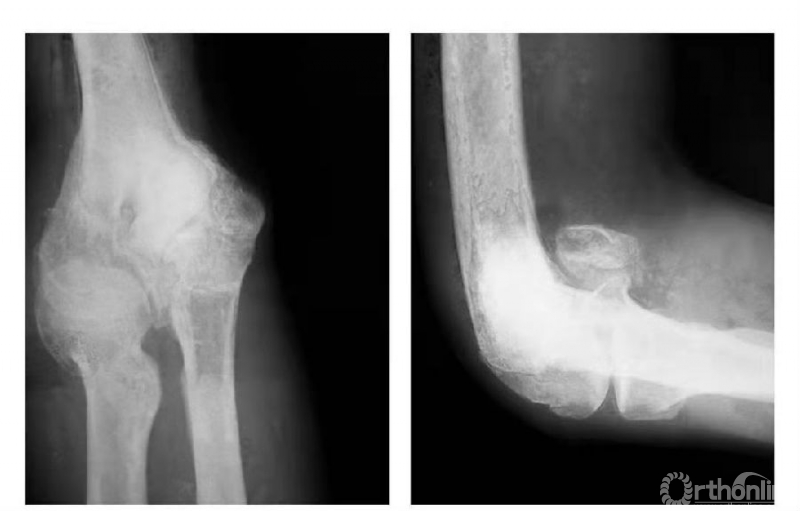

例1:肱骨内髁滑车关节面骨折,骨块陷入鹰嘴窝内,致肘内翻畸形(图4)。

图4

例2:肱骨内髁滑车关节面骨折,骨块嵌夹在尺肱关节间,且有翻转现象(图5)。

图5